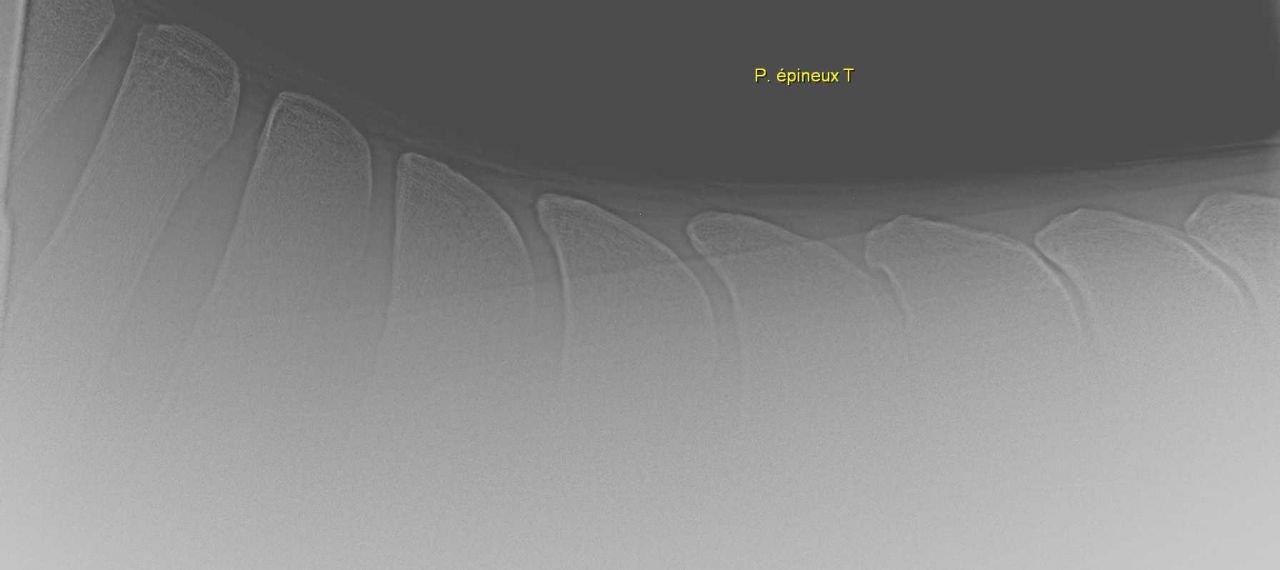

| Dire merci | Hello ! Pour ceux qui se souvienne j'avais fais un post à propos des allures de mon cheval, vous aviez été nombreux à me répondre et vos avis sur mes questionnements étaient on ne peut plus intéressants ! Je réitère donc l'expérience, tjrs concernant la patho de mon cheval. Cette fois je ne vous la cache pas : il a une malformation dorsale congénitale créant alors des CPE localisé dans la cage thoracique. les bilans ostéopathiques révèlent à chaque séance : -une compression thorax-lombaire à cause d'une certaine lordose : donc T18/L1 en compression -ainsi qu'une rotule droite sensible à cause d'un tassement inter-tarsien et tarso-métatarsien dans le jarret postérieur droit (avec sous-entendu un début d'arthropathie dégénérative très modéré) Je remets la radio de son dos datant de fin mai 2011 Maintenant je me questionne sur l'évolution de son dos. Je travaille d'arrache-pied pour le muscler et l'aider du mieux possible. Actuellement , je suis incapable de confirmer visuellement que son dos "remonte", même si les bilans ostéo et véto sont optimistes en soulignant une nette progression musculaire dorsale et un réel réalignement du bassin, le tout dans une meilleure dynamique. Voici 1 photo de lui à 2ans et demi/ 3ans : ![]() et en voici d'autres de lui, je passe les détails des autres années qd même : 2009 lors d'un stage intensif de dressage au boulot +++ pdt 6 semaines ![]() 2010 lors d'un stage/débourrage éthlogie+CSO au travail +++ pdt 6 semaines également ![]() Plus récemment, au printemps 2011, au pré pépére (d'omù le gros bide ) avant même de connaître sa patho![]() début été 2011 au début de son stage de rééducation musculaire ![]() Tjrs l'été, milieu de son stage ![]() Automne, fin du stage, retour au pré pour 1 mois et demi. ![]() Et là il est de nvx à l'écurie pour la rééduc. mais je n'ai aucune photo en claire à montrer par contre. Soit mon jugement perso, qui n'est pas très convainquant me dit que son dos était "mieux" qd il avait 3 ans .... ![]() je suis incapable de juger les éventuelles différences, s'il y a, sur les photos à dater de 2009. d'après votre oeil perso de cavalier, est ce parce que justement aucun changement n'est visible comme ça ?? merci de me donner vos avis sur la question. Désolée pour la multitude de photos, mais valait mieux que je vous en mette assez pr avoir un avis précis encore merci si vs avez des idées |

| Dire merci | Gypsie : mùerci de ton avisJ'ai commencé par un ostéo direct ![]() C'est dommage que celle ci n'ai pas donné un bon diagnostic... j'ai pris assez cher je pense à cause de ça. Il était vu tout les 6 mois depuis ses 3 ans par la même ostéo.bref c'est fait. Quant au boulot je pense l'écouter honnêtement.Et non je ne fais pas de rééduc ++ et retour au pré lambda sans taf, ça c'est ce que tu as pensé. Il est au travail journalier régulier avec un programme de rééducation musculaire tendant à faire évoluer la musculature de son dos positivement, mais de façon progressive. Soit un travail régulier mais peu intensif. Suivi par un cavalier pro, deux vétos et un ostéo. Dc pas de soucis là de soucis, je suis plus qu'à son écoute même. et les radios, j'ai tout fait faire chez moi, j'ai fais une dizaine de clichés, j'ai fais venir les vétos et le matos chez moi, c'était pas moins cher, mais + simple. |